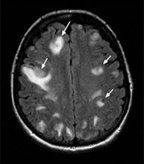

MRI of brain metastases; source: Rao, et al.